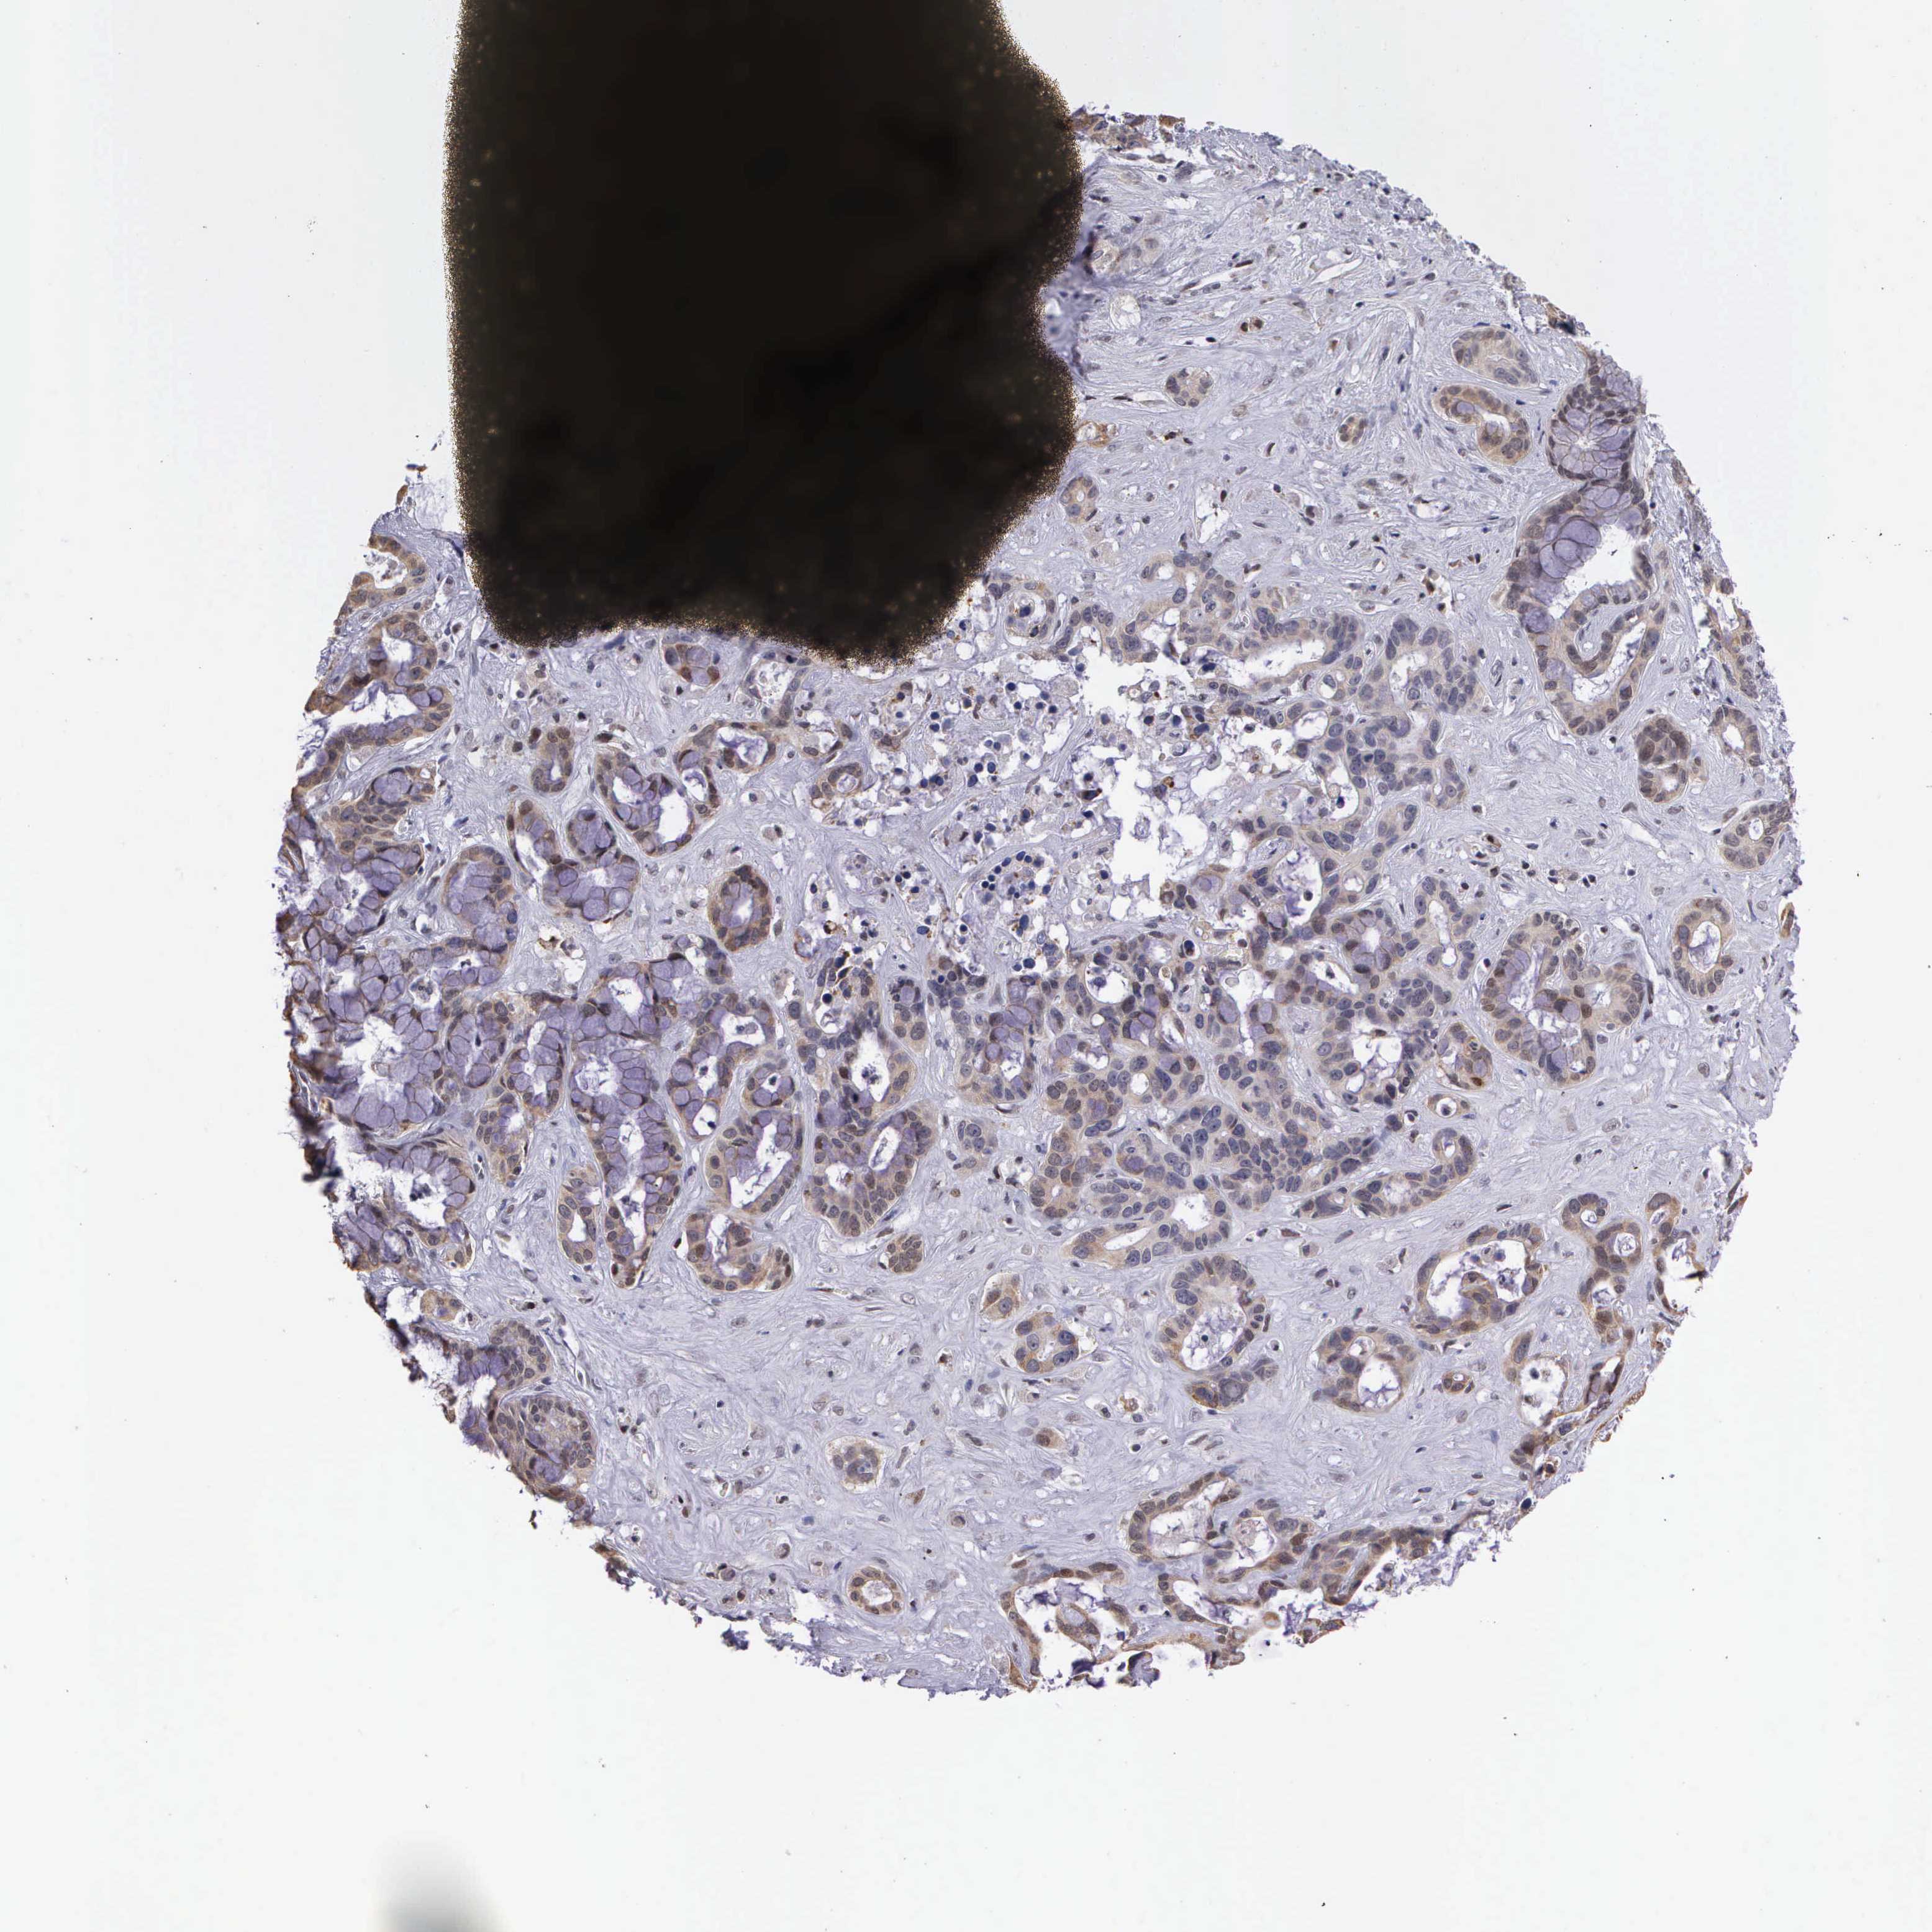

LIVER CANCER - Protein expressioni

A mouse-over function shows sample information and annotation data. Click on an image to view it in a full screen mode. Samples can be filtered based on level of antibody staining by selecting one or several of the following categories: high, medium, low and not detected. The assay and annotation is described here.

Note that samples used for immunohistochemistry by the Human Protein Atlas do not correspond to samples in the TCGA dataset.

Antibody stainingi

Antibody staining in the annotated cell types in the current human tissue is reported as not detected, low, medium, or high, based on conventional immunohistochemistry profiling in selected tissues. This score is based on the combination of the staining intensity and fraction of stained cells.

Each image is clickable and will lead to virtual microscopy that enables deeper exploration of all samples and also displays staining intensity scores, fraction scores and subcellular localization as well as patient and tissue information for each sample.

Antibody HPA000662

Staining

High

Medium

Low

Not detected

Intensity

Strong

Moderate

Weak

Negative

Quantity

>75%

75%-25%

<25%

None

Location

Nuclear

Cytoplasmic/membranous

Cytoplasmic/membranous,nuclear

Carcinoma, Hepatocellular, NOS